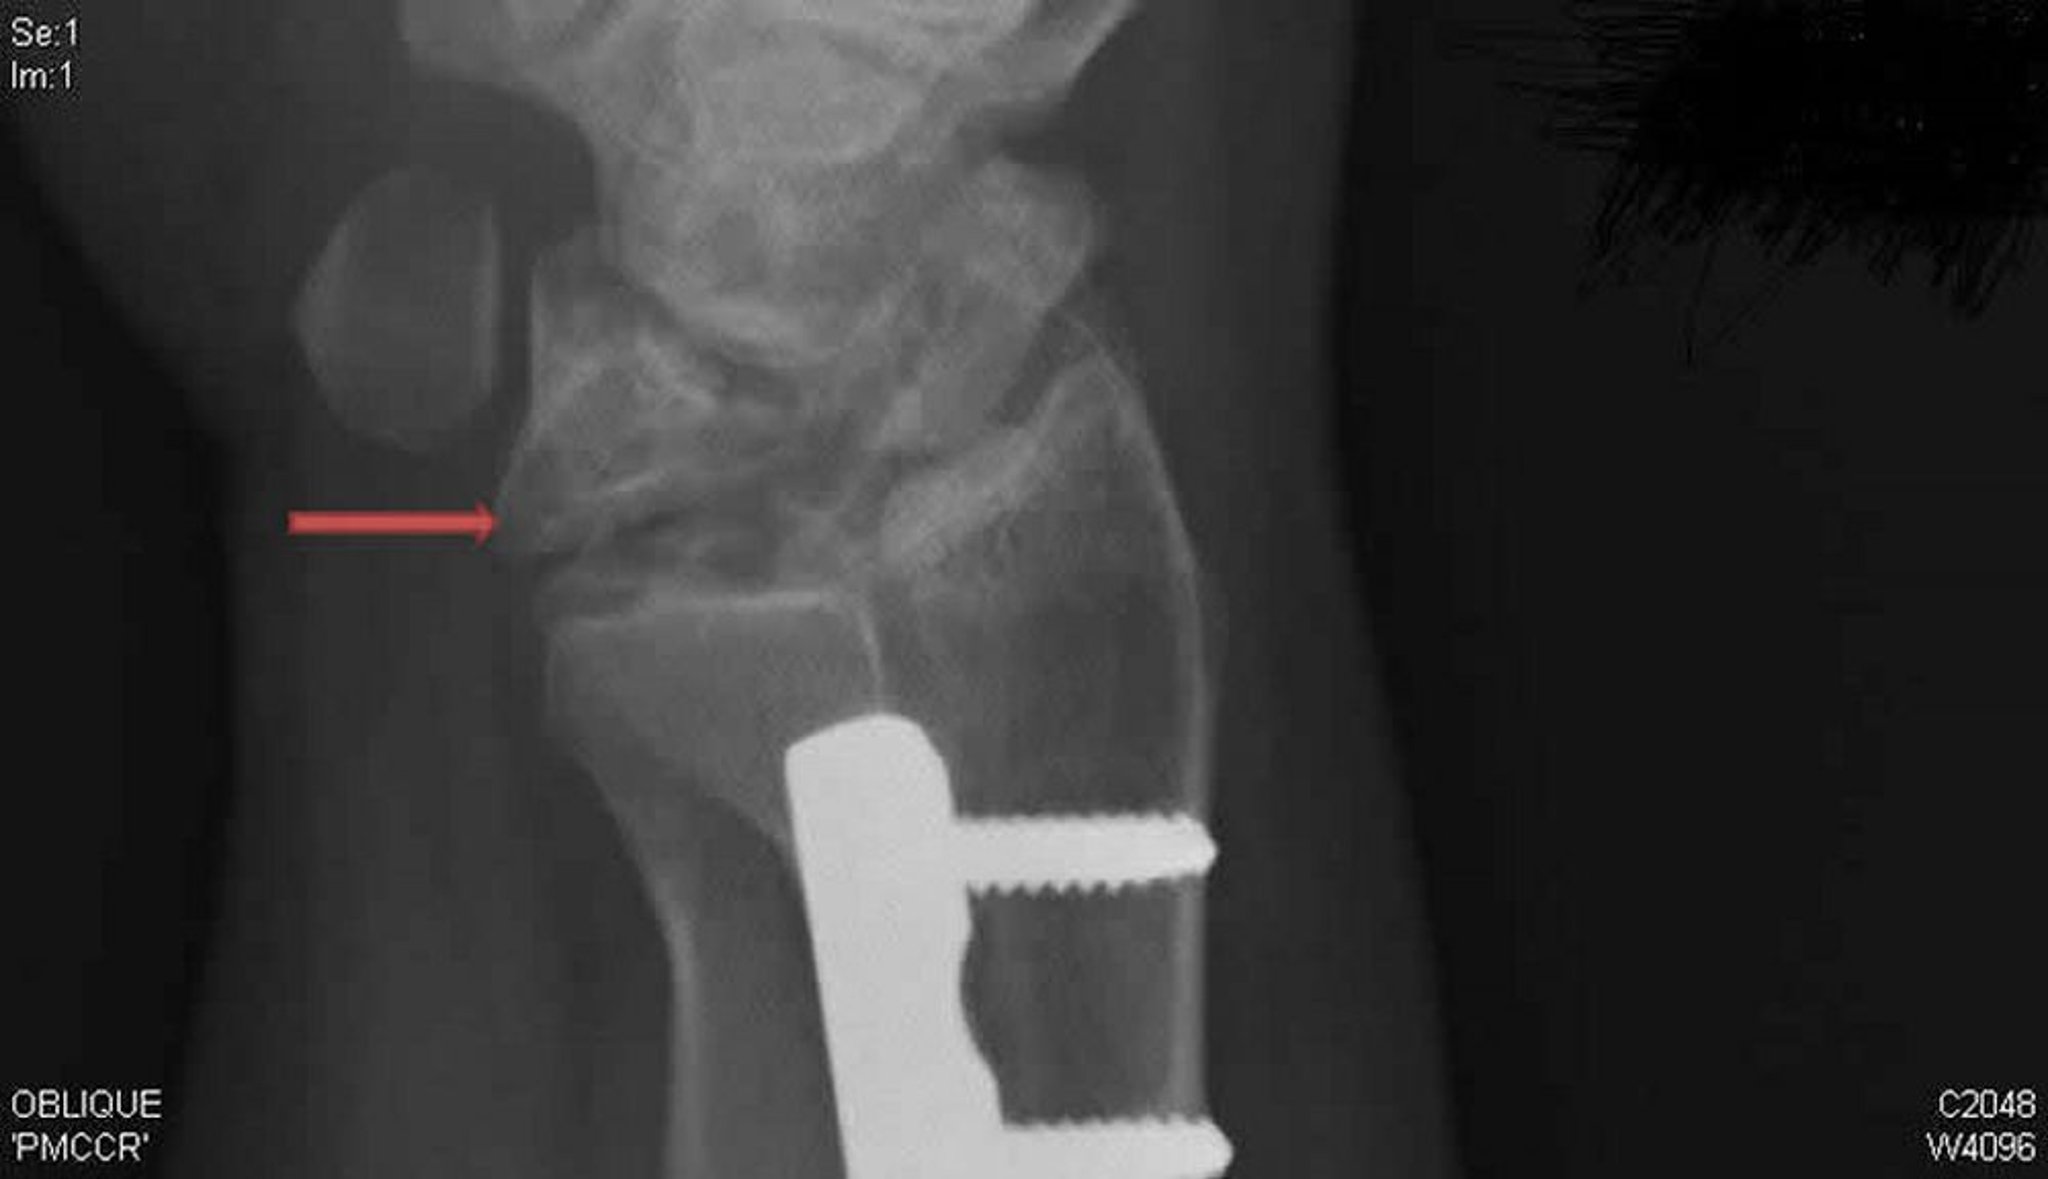

Maladie de Kienböck (radiographie oblique)

Cette radiographie oblique du poignet droit montre une maladie de Kienböck. Noter l'effondrement et la fragmentation de l'os lunaire (flèche), qui n'était pas visible sur l'incidence de face.

Rx courtoisie de David R. Steinberg, MD.